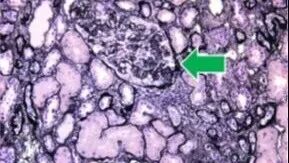

一名40岁女性,因“泡沫尿及血压升高2个月”就诊,既往有银屑病史,否认家族中有明确肾脏疾病史。入院检查提示:患者存在大量蛋白尿,血清白蛋白降低,肾功能明显受损。在排除继发性肾病后,患者接受了肾穿刺活检,病理诊断为局灶节段性肾小球硬化(FSGS)。

结合肾穿刺标本的电镜复核,发现足细胞及肾小管上皮细胞内可见少量形态异常的线粒体,最终明确诊断为CoQ8B肾病。